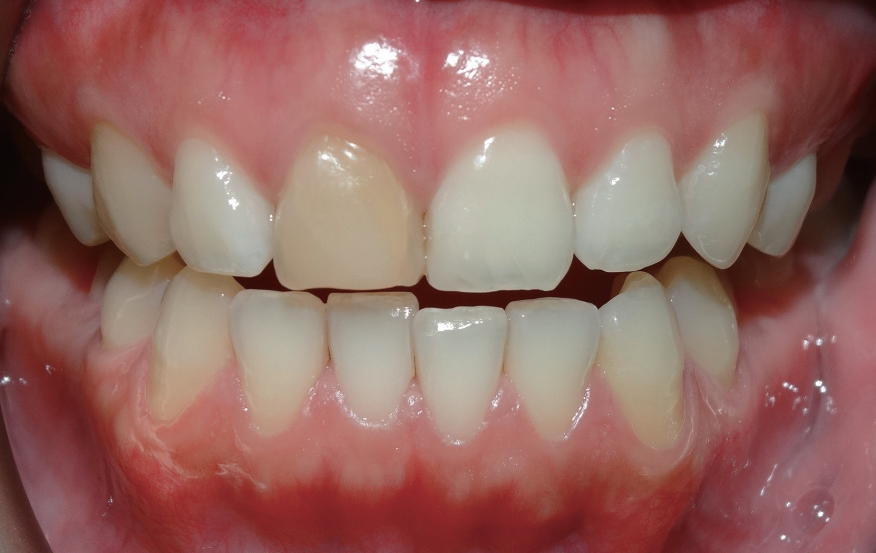

口腔检查   触、扣 诊时,患者表示11较邻牙相比敏感,牙周探诊无异常,肉眼可见11牙冠颜色泽确实和邻牙有所差异(图1),且其唇侧面有数条明显裂纹,而在11的敲扣声音也不像邻牙那般清脆响亮。

图1 11 牙冠颜色相较邻牙暗黄,患者自述按压根部牙龈时略感不适